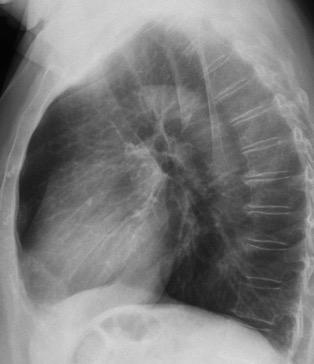

Raro. (2-9% de los T. tímicos). Asintomático. Contiene grasa (hasta 90%) y tejido timico (10-33%). Pueden ser muy grandes y confundirse con cardiomegalia. La tomografía “clásica” muestra los límites de la silueta cardiaca. (flechas)

Líneas paraespinales formando un “paréntesis” por encima del diafragma. El signo señala el origen “intratorácico” de la lesión.